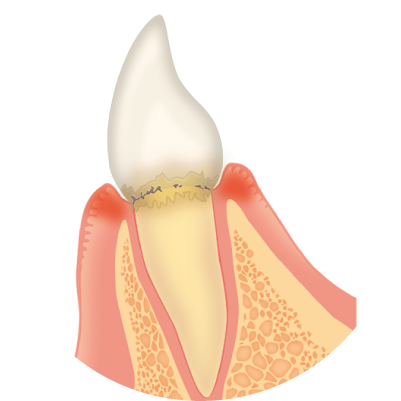

歯茎の溝(歯周ポケット)に隠れたプラーク(細菌の塊)によって発症します。歯垢は歯ブラシやうがいである程度落とすことはできますが、全て取り除くことは不可能と言われていおり、磨き残された歯垢はやがて歯石となってしまいます。歯石には小さな穴や隙間があり、そこが新たな細菌の住処となります。こうして細菌はどんどんお口の中で繁殖し、歯周病は悪化していきます。

はじめは歯茎だけが腫れる歯肉炎に、そしてこの状態のまま放置すると、歯を支える歯槽骨が溶けてしまう歯周炎へと進行します。歯茎から血や膿が出たり、歯がぐらついて噛みにくく、口臭もひどくなっていきます。

歯周病にかかった状態